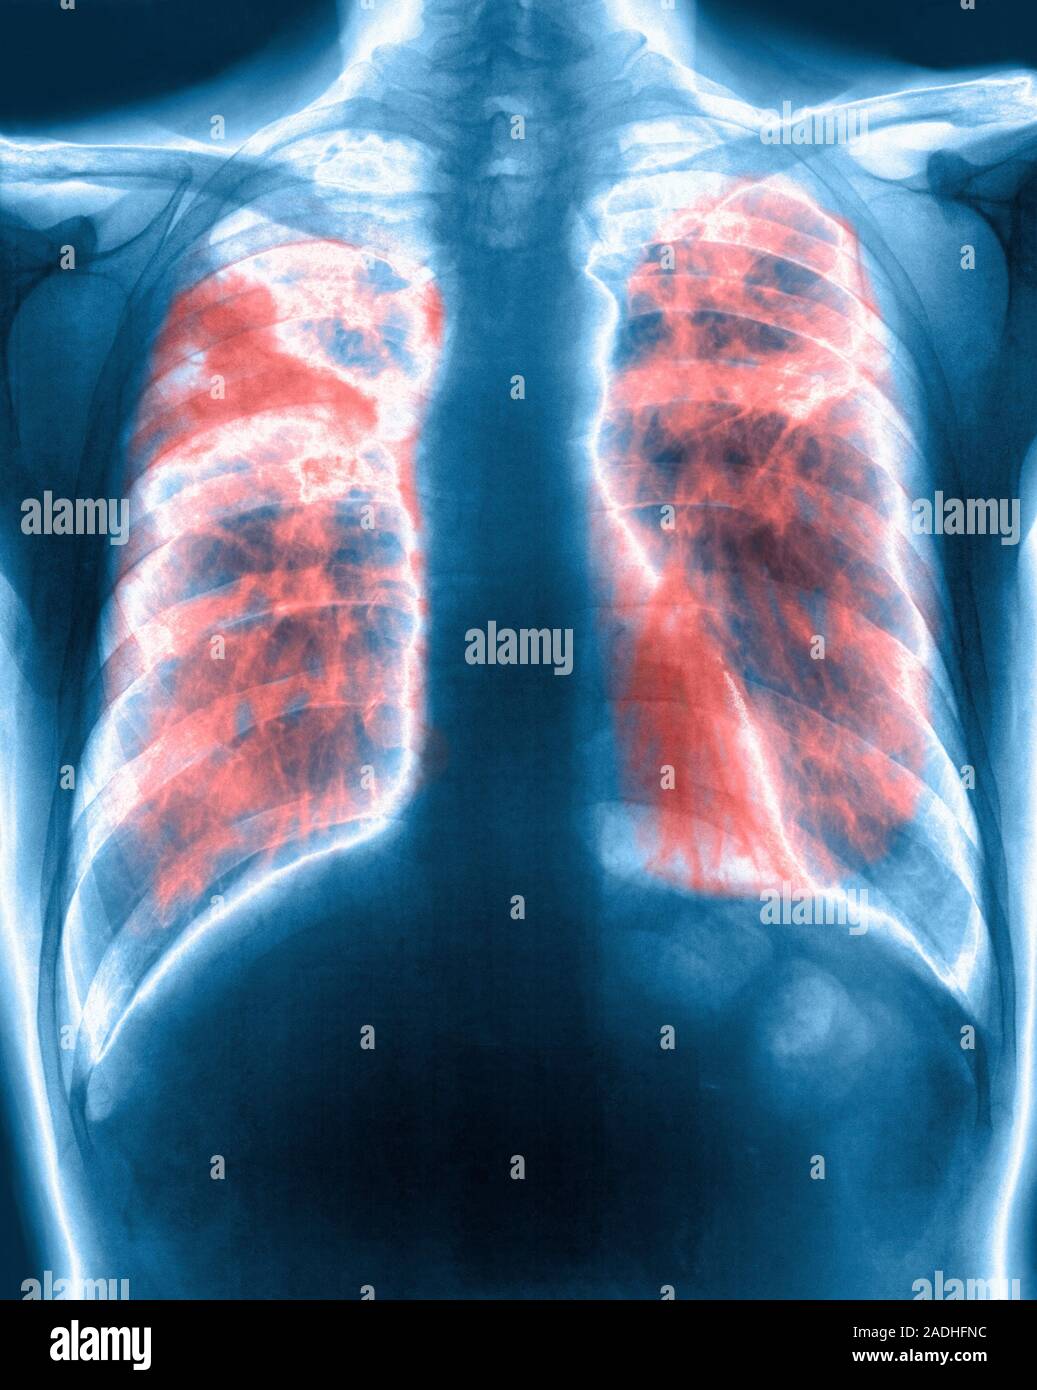

From www.alamy.com

Lung fibrosis. Coloured Xray of the chest of a patient with pulmonary (lung) fibrosis, or Fiberglass Pulmonary Fibrosis Pulmonary fibrosis (pf) is a chronic, progressive lung disease marked by excessive accumulation of. exposure to fiber glass has been shown to induce pleural and lung disorders such as emphysema, fibrosis. Having pulmonary fibrosis can cause fear,. inhalation of grp, independent of environmental concentration, causes alterations of the cellular and humoral components. the best judgement was that. Fiberglass Pulmonary Fibrosis.